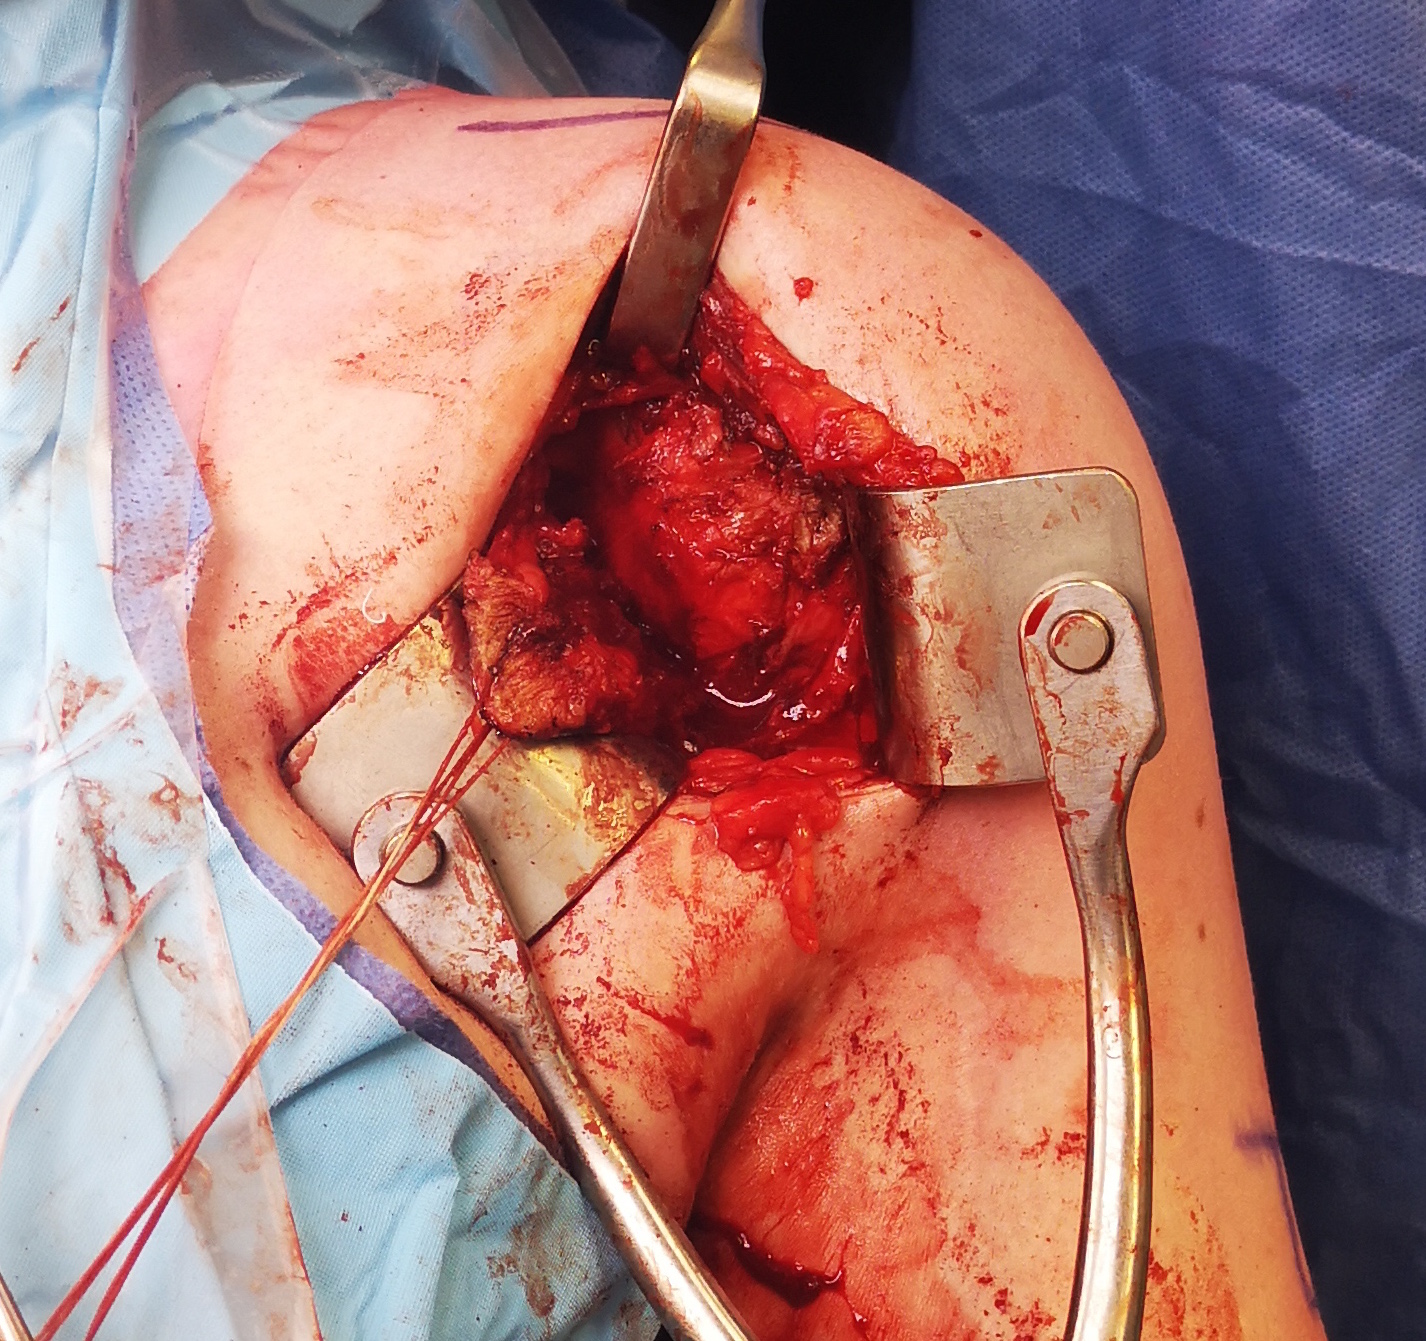

Deltopectoral approach

- split subscapularis

- can perform subscapularis tenotomy and later tighten / Putti Platt

- T shape capsulotomy of capsule

- vertical component on articular margin humeral insertion all the way posterior

- transverse component to midpoint glenoid making superior and inferior flaps

- superior advancement inferior capsular flap

- eliminate inferior pouch and reduce posterior capsular redundancy

- then suture down superior flap

+/- allograft reconstruction

+/- subscapularis shift / Putti-Platt